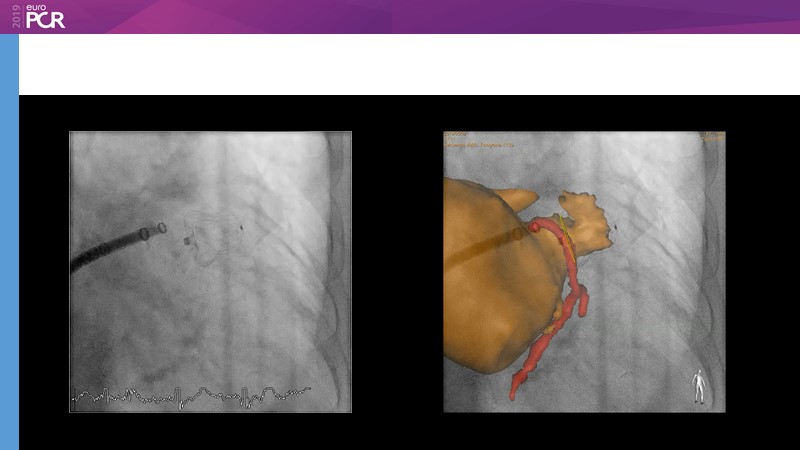

Optimising procedural outcome and safety

Previous Next